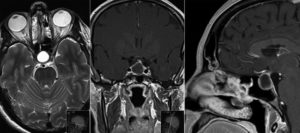

Если предполагается злокачественный характер опухоли, показана консультация онколога. Один из самых информативных методов диагностики – МРТ исследование, которое позволяет дифференцировать кисту, сформировавшуюся в зоне кармана Ратке, от таких патологий, как арахноидальные кисты или аденомы гипофиза (пролактиномы).

На снимке отчетливо видно хорошо отграниченное новообразование кистозной структуры округлой или продолговатой формы иногда с утолщенной стенкой. КТ-томография показывает большую плотность ткани кисты по сравнению с окружающей мозговой тканью.

Компьютерная томография

Киста кармана Ратке при компьютерной томографии характеризуется как кистозное образование селлярнй или супраселлярной локализации, с четкими границами, сниженной плотности. Крупные размеры могут приводить к ремоделированию прилежащих костей.

Простые кисты могут быть неотличимы от арахноидальных кист и эпидермоидов. Комплексные кисты могут быть неотличимы от краниофарингиомы или аденомы гипофиза.

За счет вариабельности в визуализации компьютерную томографию нельзя использовать как единственный метод диагностики.

- нативно

- однородное гипоинтенсивное образование, обычно не содержащее кальцинатов

- иногда может иметь смешанную изо- гипоинтенсивную плотность

- постконтрастные изображения: отсутствие контрастного усиления

Магнитно-резонансная томография

Кисты кармана Ратке почти всегда имеют гомогенную интенсивность МР сигнала, в то время как кистозные краниофарингеомы и аденомы с кровоизлиянием имеют гетерогенный сигнал. [9] Уровни жидкости подразумевают кровоизиляние в анамнезе. Хотя кисты кармана Ратке не имеют характерных только для данной нозологии МР признаков. Большинство кист можно отнести к двум группам:

- Кисты кармана Ратке с низкой интенсивностью МР сигнала на Т1 взвешенных изображениях и высокой интенсивностью сигнала на Т2 взвешенных изображениях,

- Кисты кармана Ратке с высокой интенсивностью МР сигнала на Т1 взвешенных изображениях и различной интенсивностью МР сигнала на Т2 взвешенных изображениях

В первой группе содержимое кисты серозное и имеет сигнальные характеристики соответствующие ЦСЖ. Во второй группе содержимое кист богато мукополисахаридами, которые считаются продуктами муцин-продуцирующих клеток в стенке кисты.

В редких случаях повышенный сигнал на Т1 взвешенных изображениях сочетается с низким МР сигналом на Т2 взвешенных изображениях за счет комбинации факторов включающих наличие мукополисахаридов, продуктов распада гемоглобина, высокого содержания холестерола и сушенных клеточных масс.

Главным методом для обнаружения кисты является магнитно-резонансная или компьютерная томография. Так как это образование похоже на аденому гипофиза и краниофарингиому, то чаще всего необходимо дополнительное введение контрастного вещества. К наиболее важным диагностическим критериям кисты кармана Ратке относятся:

- расположение внутри турецкого седла, или она выходит и за его границы;

- форма – овал, гантель, круг;

- находится между передней и средней долей;

- размер обычно 1-2 см, реже бывают крупные – до 4-5 см, они могут разрушать костные ткани;

- при введении контраста не накапливает его;

- границы четкие;

- однородной структуры;

- не содержит отложений кальция в отличие от опухолей.

На снимке МРТ стрелочками указана киста и аденогипофиз, который всегда деформирован кистой, и киста непосредственно к нему прилегает

Плотность содержимого кисты ниже, чем окружающая ткань, если преобладает жидкостный компонент внутри. При усиленном накоплении белков и мукополисахаридов консистенция становится желеобразной. В редких случаях имеется неоднородность сигнала за счет того, что присутствуют включения жиров, распавшейся крови, слущенного слоя эпителия, который выстилает изнутри кисту.

Окружающая ткань гипофиза может выглядеть более плотной, так как отмечается сдавление его клеток. При аденоме, наоборот, соседние области разрежены, так как максимальная гормональная активность наблюдается внутри опухоли.